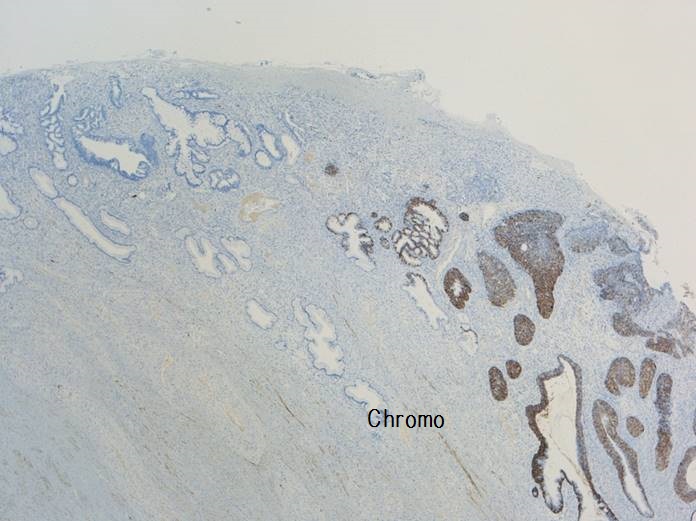

子宮頸部のSCJにおいてクロマチン増量を示す異型上皮が明瞭な

腺管構造や充実性胞巣構造を形成し増生していた。充実性増生を示す成分はN/C比や核分裂像が目立ち、免疫染色ではsynaptophysin、chromogranin A、CD56が陽性であり神経内分泌分化が示唆された。以上の所見より、神経内分泌癌成分を伴う腺癌と診断された。面積的には腺癌成分が8割で神経内分泌癌成分は2割であった。腺癌成分で微小浸潤がみられたが神経内分泌癌成分はin situであった。

腺管構造や充実性胞巣構造を形成し増生していた。充実性増生を示す成分はN/C比や核分裂像が目立ち、免疫染色ではsynaptophysin、chromogranin A、CD56が陽性であり神経内分泌分化が示唆された。以上の所見より、神経内分泌癌成分を伴う腺癌と診断された。面積的には腺癌成分が8割で神経内分泌癌成分は2割であった。腺癌成分で微小浸潤がみられたが神経内分泌癌成分はin situであった。